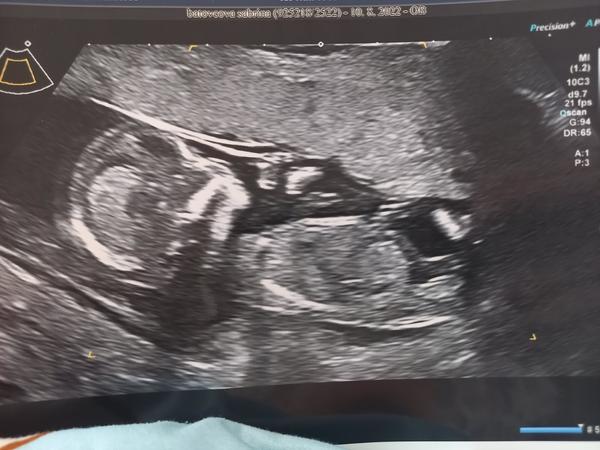

Vidíte pohlavní hrbolek na 1. screeningu?

Ahoj, dne 10.8. jsem byla na 1.screeningu, byla jsem ten den 13+1. Pohlaví si asi neplánuji říct,ale i tak dumám pořád nad těmito fotkami a snažím se najít třeba pohlavní hrbolek. Pro zkušenější, nevidíte tam hrbolek,popř. co byste hádali?🙊